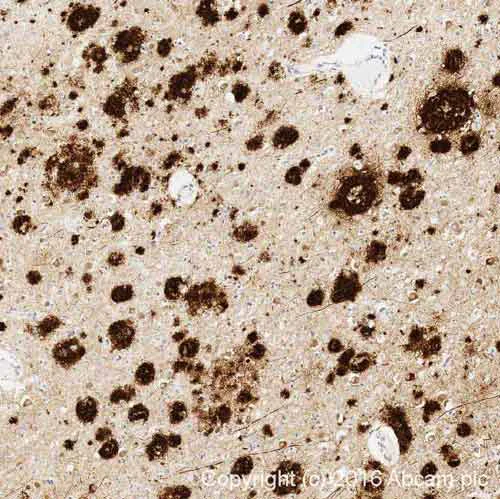

Immunohistochemistry (Formalin/PFA-fixed paraffin-embedded sections) - Anti-Amyloid Fibril antibody [mOC22] - Conformation-Specific (AB205339)

IHC image of Amyloid Fibril staining in Human Brain Alzheimer formalin fixed paraffin embedded tissue section* performed on a Leica Bond™ system using the standard protocol F. The section was pre-treated using heat mediated antigen retrieval with sodium citrate buffer (pH6 epitope retrieval solution 1) for 20 mins. The section was then incubated with ab205339 0.1μg/ml for 15 mins at room temperature and detected using an HRP conjugated compact polymer system. DAB was used as the chromogen. The section was then counterstained with haematoxylin and mounted with DPX.

For other IHC staining systems (automated and non-automated) customers should optimize variable parameters such as antigen retrieval conditions primary antibody concentration and antibody incubation times.

*Tissue obtained from the Human Research Tissue Bank supported by the NIHR Cambridge Biomedical Research Centre